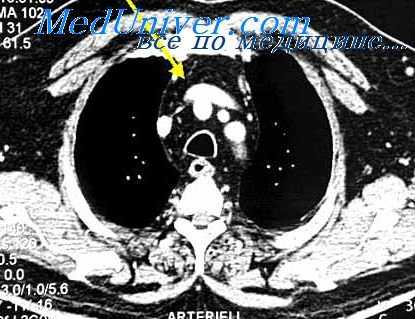

Больной Е., 25 лет, ранен в грудь осколком мины 25/11 2012 г. Поступил в госпиталь через 20 часов в тяжелом состоянии, с выраженным цианозом, одышкой. Пульс 110 ударов в минуту, ритмичный, артериальное давление 120/70 мм ртутного столба, температура 38°. В области рукоятки грудины рана длиной 0,7 см, закрытая сгустком крови. Отека окружающих тканей не отмечается. На рентгенограмме осколок 0,5 см длины располагается в переднем средостении кпереди от дуги аорты. Вокруг него отмечается диффузное затемнение, распространяющееся на корень левого легкого. Выражен симптом Хорнера.

Больной находился в госпитале в течение 5 дней. Постепенно температура снизилась до нормы, исчезла тахикардия и одышка, но симптом Хорнера остался. Больной эвакуирован в хорошем состоянии.

В данном случае имело место слепое ранение средостения, без повреждения крупных сосудов и органов. Течение этого вида травмы было благоприятным, инородное тело в дальнейшем может быть удалено, если появятся жалобы на боли, сердечные нарушения, повышения температуры, зависящие от коррозии металла и инфицирования зоны ранения.